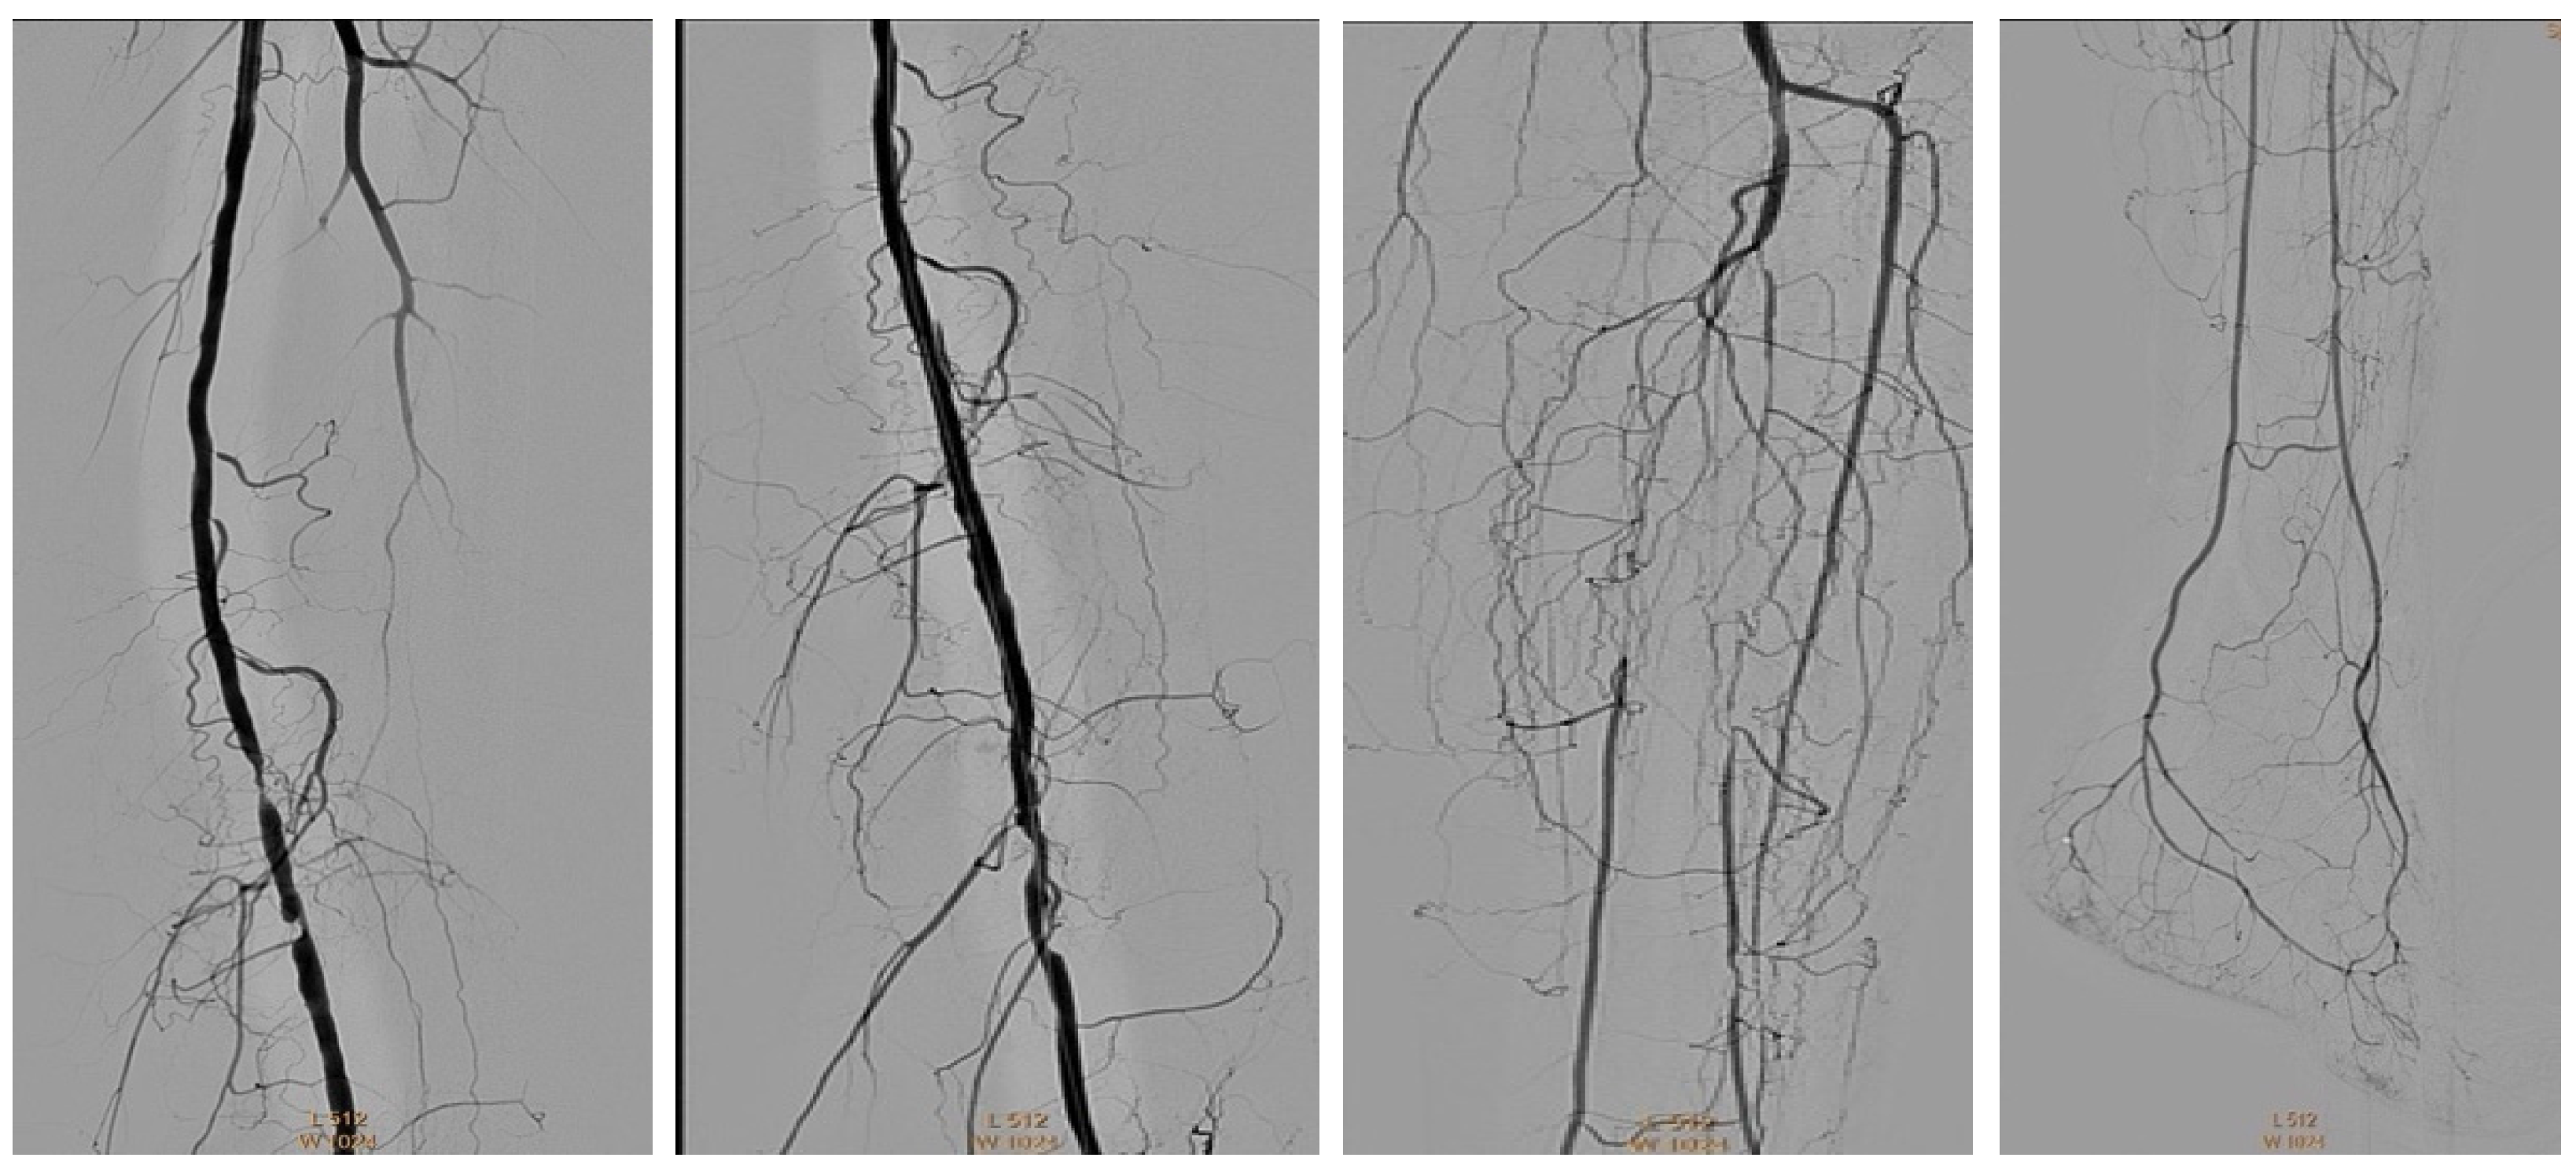

4.1. Case 1—Direct Revascularization-Minor Amputation

4.2. Case 2—Indirect Revascularization-Major Amputation